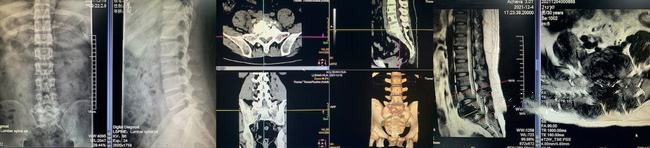

△术前检查影像学

患者是一位风华正茂的30岁小伙,2个多月来,腰痛并且有右下肢麻木胀痛的情况,最近一个星期甚至只能瘸腿走路,已经严重影响生活,于是到南溪山医院就诊,经过检查,医生发现他的右下肢小腿外侧及足背足底及足趾皮肤感觉明显减退,初步诊断为腰骶椎结核,腰5/骶1出现严重的骨质破坏,结核脓肿向后明显压迫神经,医生为他进行足疗程抗结核治疗后,经脊柱外科专家团队讨论,决定为他进行手术治疗。

△3D打印模型

为了手术更精准,取得更好地疗效,脊柱外科团队联合该院3D打印中心技术人员,共同为该患者制定了个性化的手术方案,脊柱外科顺利为他完成了3D打印模型辅助下腰椎结核病灶清除和脊柱稳定性重建术,术后5天该患者就能佩戴支具下床活动了,仅一个星期就出院了,术后效果超乎预期。经过术后复查,该患者腰骶椎结核病灶清除干净,对植骨也很满意,脊柱内固定位置佳,稳定性好。腰疼腿麻的症状基本消失,他称赞脊柱外科让自己获得了新生。